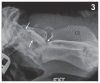

Figure 3

Myelogram showing subarachnoid contrast distribution. Myelogram in lateral position with limited extension of the neck. Note abrupt interruption of contrast columns at the level of the atlas vertebral body (dorsal and ventral shown by first 2 white arrows on the left), and marked attenuation of the dorsal contrast column at the level of the atlas and axis [third white arrow (right of image)].